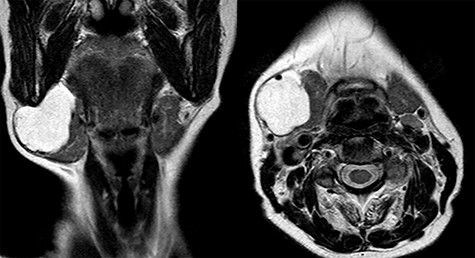

Magnetic resonance imaging (MRI) was performed and showed a cystic mass of 4 × 4 × 3.5 cm in size located under the right mandible and strictly adherent to the submandibular gland. On T2-weighted images, the mass resulted hyperintense, while hypointense in those T1 weighted (Fig. 2).